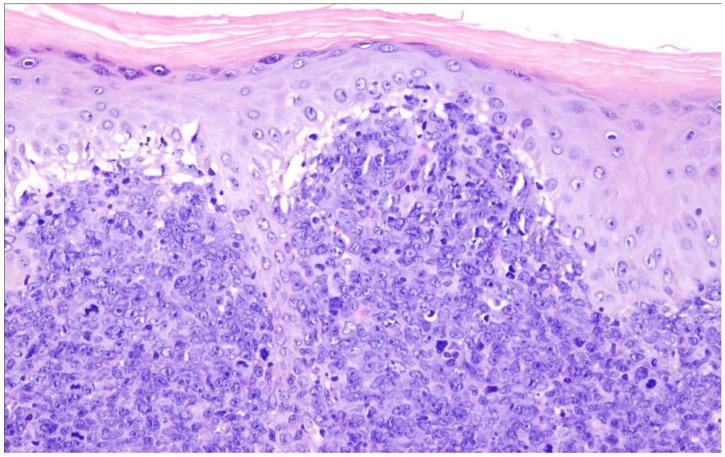

The family/class of the large B-cell lymphomas (LBCL) in the 5th edition of the World Health Organization (WHO) classification of haematolymphoid tumors (WHO-HAEM5) features only a few major changes as compared to the 4th edition. In most entities, there are only subtle changes, many of them only representing some minor modifications in diagnostic terms. Major changes have been made in the diffuse large B-cell lymphomas (DLBCL)/high-grade B-cell lymphomas (HGBL) associated with and and/or rearrangements. This category now consists of and rearranged cases exclusively, while the double hit lymphomas now constitute genetic subtypes of DLBCL, not otherwise specified (NOS) or of HGBL, NOS. Other major changes are the conceptual merger of lymphomas arising in immune-privileged sites and the description of LBCL arising in the setting of immune dysregulation/deficiency. In addition, novel findings concerning underlying biological mechanisms in the pathogenesis of the different entities are provided.

在世界卫生组织(WHO)血液淋巴系统肿瘤分类第5版(WHO-HAEM5)中,大B细胞淋巴瘤(LBCL)家族/类别与第4版相比仅有一些主要变化。在大多数实体中,只有细微变化,其中许多仅代表诊断术语上的一些小修改。在与 和 以及/或者 重排相关的弥漫性大B细胞淋巴瘤(DLBCL)/高级别B细胞淋巴瘤(HGBL)方面有重大变化。这一类别现在仅由 和 重排的病例组成,而 双打击淋巴瘤现在构成DLBCL、未另行特别说明(NOS)或HGBL、NOS的基因亚型。其他主要变化包括免疫豁免部位发生的淋巴瘤在概念上的合并,以及免疫失调/缺陷情况下发生的LBCL的描述。此外,还提供了关于不同实体发病机制中潜在生物学机制的新发现。